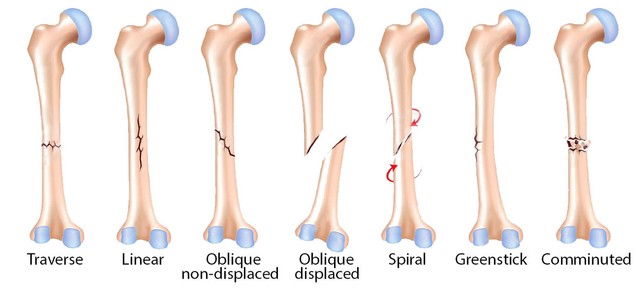

Jenis Dan Kategori Tulang Patah

Jenis Dan Kategori Tulang Patah

Topik 4 sains sukan

Fraktur - Jenis û Penyebab dan Pengobatan - IDN Medis

Fraktur - Jenis û Penyebab dan Pengobatan - IDN Medis

Bab 5 luka & patah

Bab 5 luka & patah

Sering Dialami Atlet, Ini 7 Perbedaan Patah Tulang dan Dislokasi

Sering Dialami Atlet, Ini 7 Perbedaan Patah Tulang dan Dislokasi

Ini yang Dimaksud dengan Fraktur Tulang

Ini yang Dimaksud dengan Fraktur Tulang